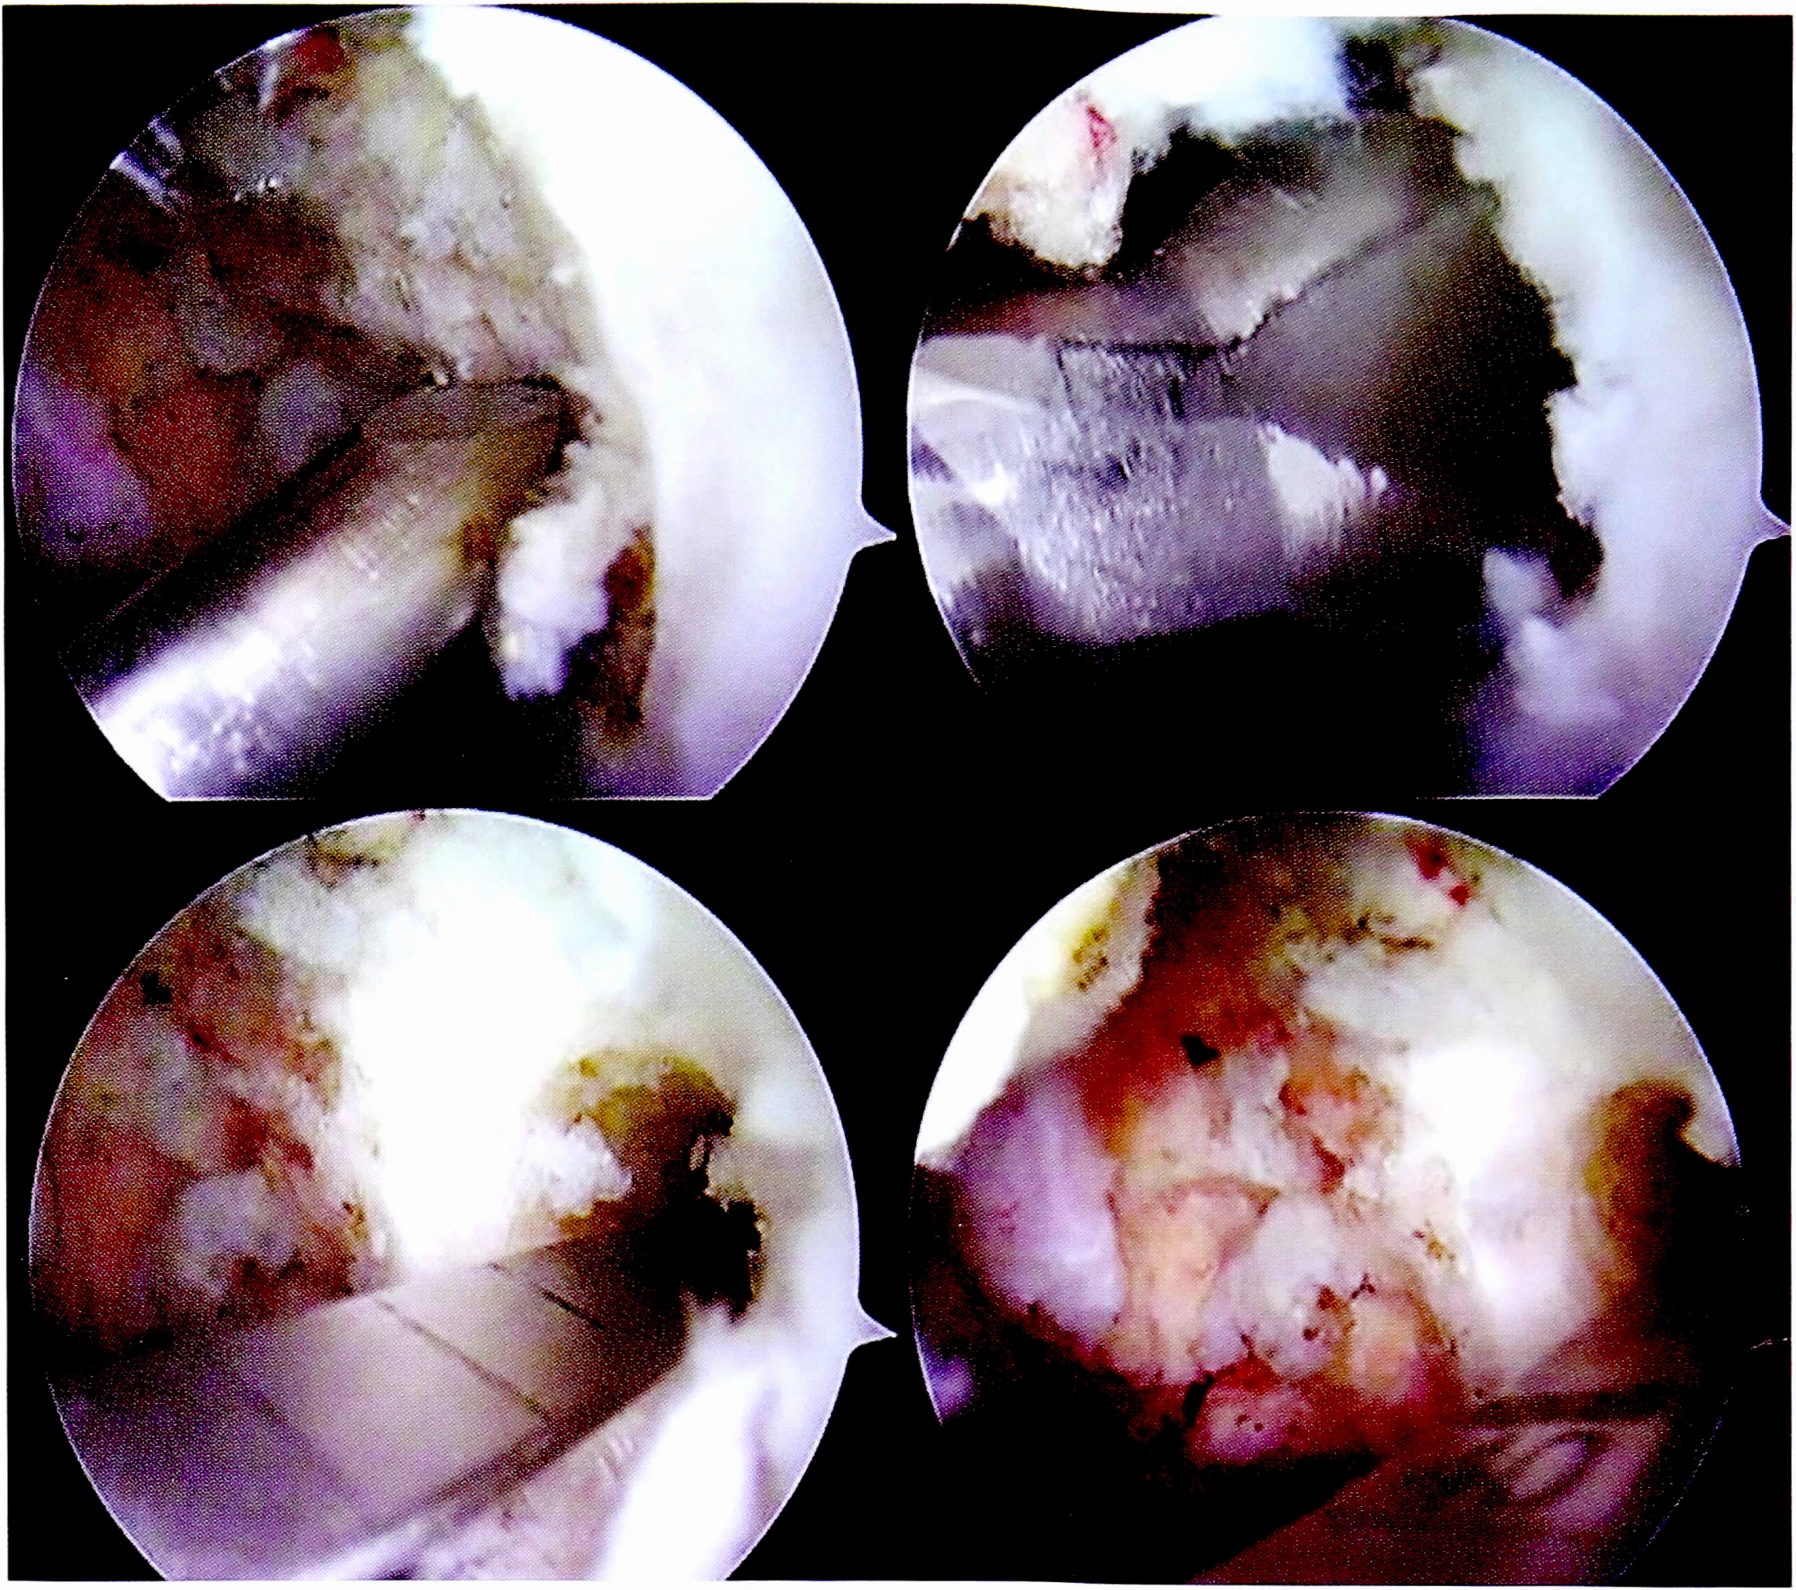

Следующим этапом осуществлялось иссечение рубцовой ткани и фрагментов поврежденных крестообразных связок в межмыщелковом пространстве. Особое внимание уделялось визуализации заднего отдела сустава и заднего межмыщелкового пространства вследствие обязательного формирования дополнительного заднемедиального порта (рис. 3).

Рис. 3. Дебридмент, резекция культи ЗКС.

Fig. 3. Resection of PCL fibers, debridment.

После проведения и фиксации на бедренной кости трансплантата ЗКС формировались костные тоннели для пластики ПКС. Использовались стандартная транстибиальная методика и набор направителей для ее выполнения (рис. 7).

Рис. 7. Артроскопическая картина основных этапов пластики ПКС.

Fig. 7. Main stages of ACL plasty.

Таким образом, костные тоннели в большеберцовой кости проводились через разноименные мыщелки: латеральный для ЗКС и медиальный для ПКС.

Следует отметить необходимость соблюдения строгой последовательности фиксации аллотрансплантатов в костных тоннелях. Авторами рекомендуется первым этапом выполнять натяжение и фиксацию в каналах трансплантата ЗКС, затем — трансплантата ПКС. Такая последовательность позволяет максимально вывести голень из заднего подвывиха. Последним этапом производится дополнительное натяжение фиксированных трансплантатов за счет самозатягивающихся петель фиксаторов в бедренных каналах.